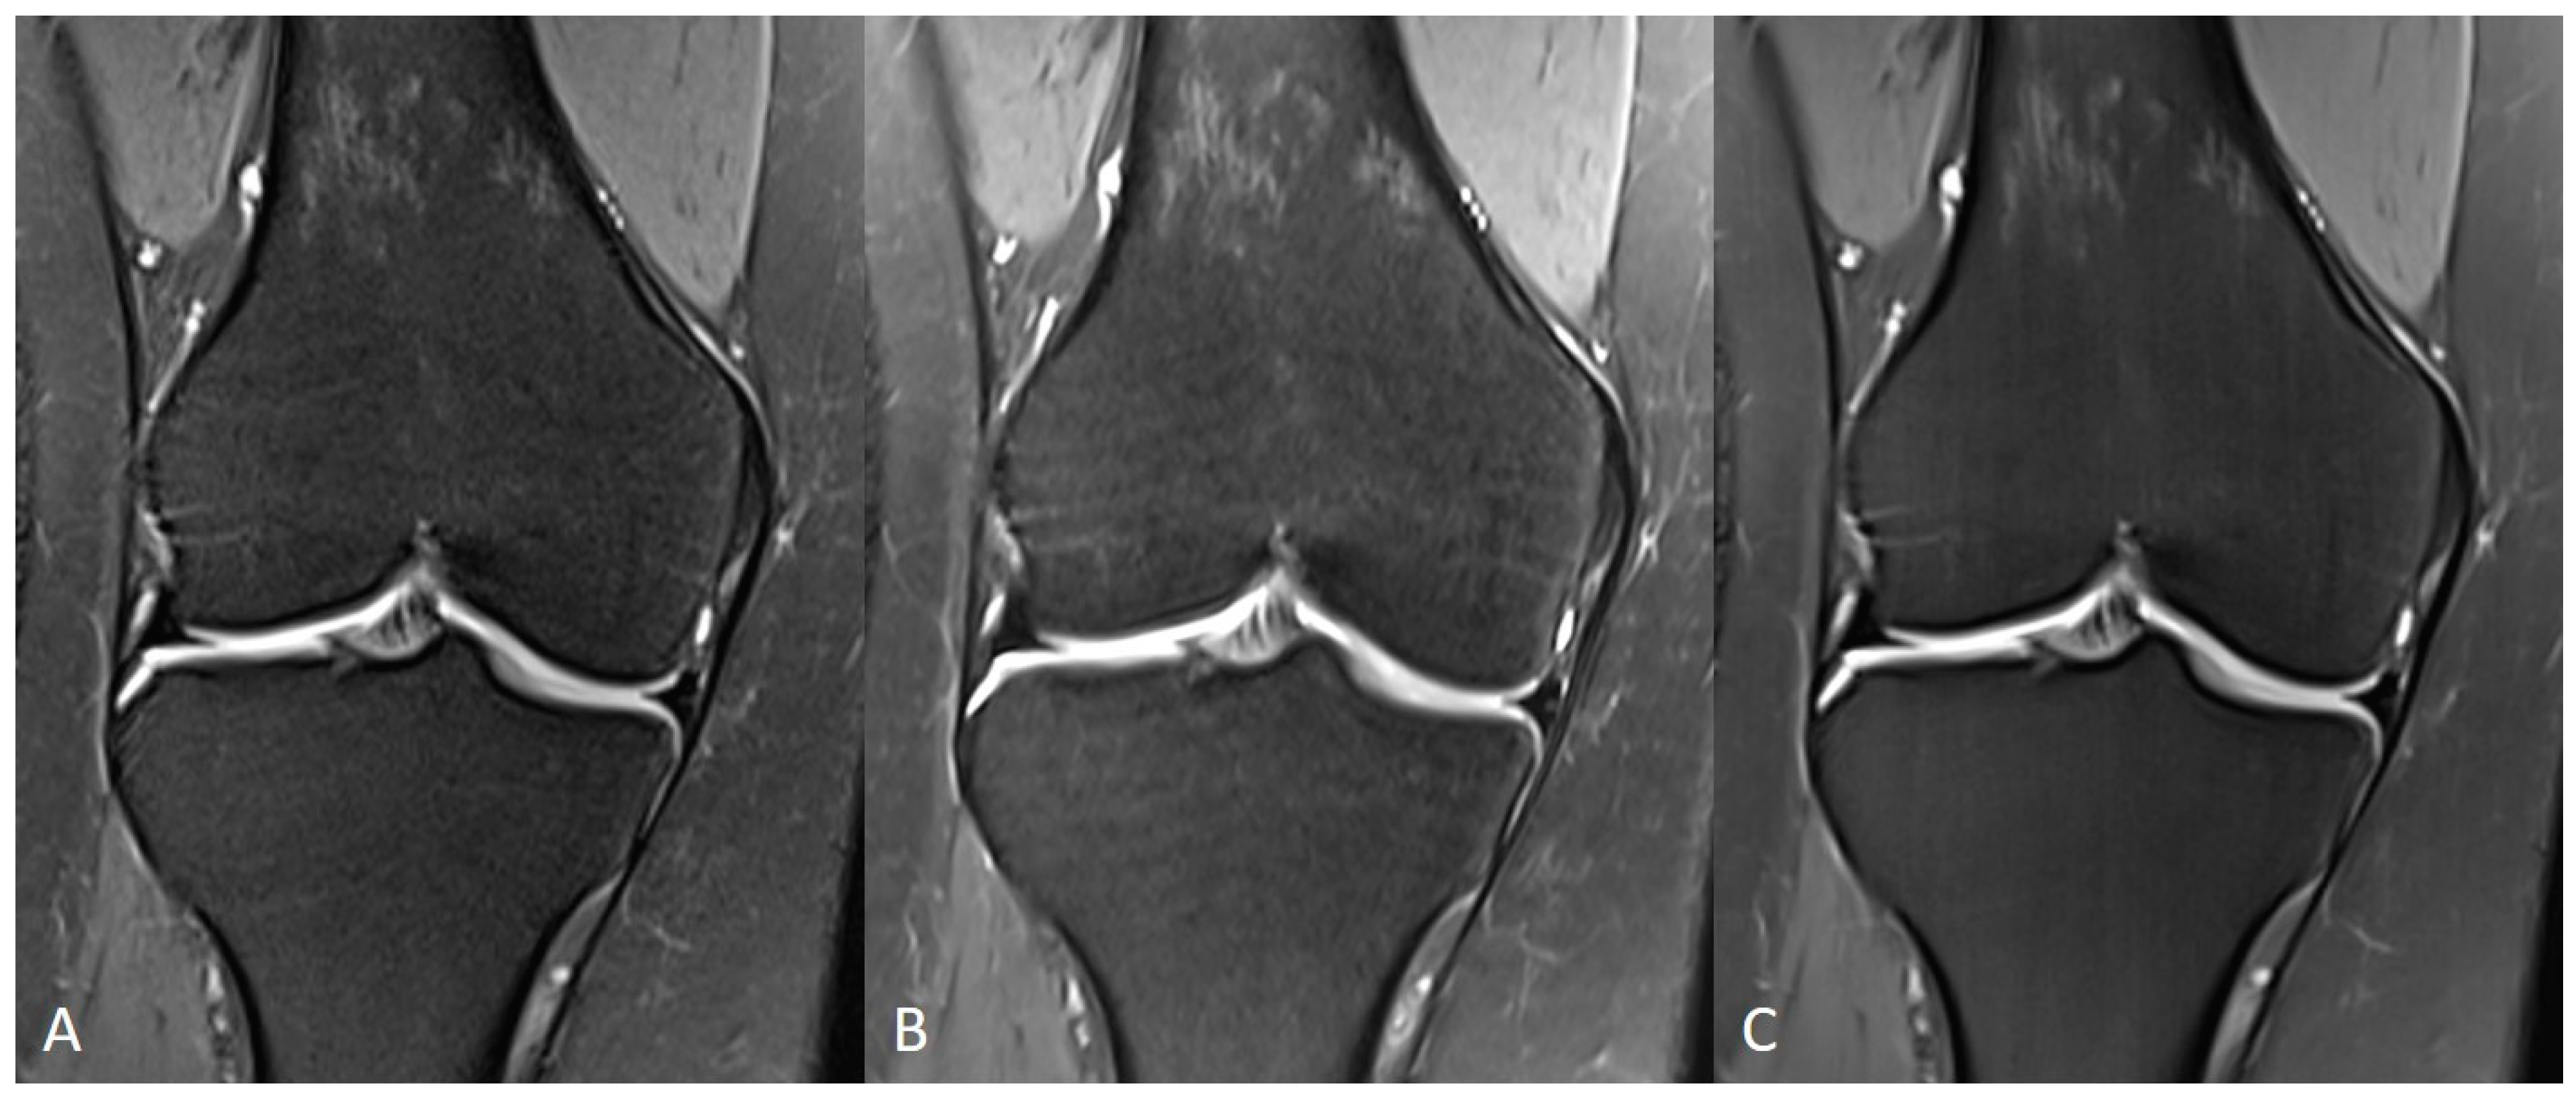

| Knee | TSES | TSE PD FS | coronal | 3:11 | 150 | 0.2 × 0.2 × 3.0 | 2 | 1 | 3 | 3790 | 44 | 150 | 100 | 14.6 |

| TSEDL | TSE PD FS | coronal | 1:33 | 150 | 0.5 × 0.5 × 3.0 | 1 | 1 | 3 | 3580 | 41 | 150 | 120 | 13.7 | |